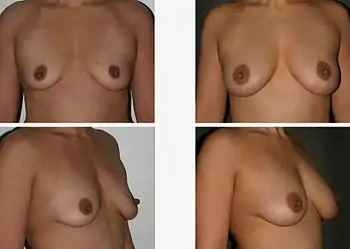

Mechanical+Enzymatic(ME) and mechanical methods are the most common isolation methods, although there is no standard method.[11] Accordingly, Dr. Glass and Ferretti proposed one of the ME methods which is to apply tumescent-assisted liposuction using a mechanical or ultrasound-assisted liposuction cannula. Through liposuction, the fat sample is digested by enzymatic activities of collagenase or trypsin in Dulbecco’s modified Eagle's medium (DMEM). The resultant tissue suspension undergoes incubation and agitation at around 37 °C and is filtered through a strainer to remove unnecessary debris. The cell pallet left after centrifugation is called SVF. The SVF is seeded on the plate, after the second suspension with bovine calf serum, 1% penicillin or streptomycin, and L-glutamine. The adherent properties of ADSCs on the plate allow isolation of ADSCs.[12] However, due to the inconvenience of isolating the pure ADSCs, a cell-assisted lipo-transfer (CAL) is more commonly used. CAL transforms poor ADSCs into enriched ADSCs by mixing isolate SVF and aspirated fat.[13] The efficacy of CAL was proven by the increased survival rate of autologous breast augmentation when introduced around 270ml for each breast.[14]

Around 1.5 million women have breast implant surgeries per year.[15] Yet the side effects of the fat transplant can be severe and cause irreversible damage to the patient's body. The most well-known side effects are foreign body sensation, calcification, fat cell necrosis, capsular construction, rupture, cysts and some fat cells leaving the implanted area.

In most cases, calcification and cysts are the biggest threat of breast augmentation surgery. Fat stem cells failed to pick up a new blood supply will die and be removed from the body by immune cells. However, when this clearing process miss removing dead cells the cluster will lead to calcification and cysts formation. These are visible on the breast as lump sometimes and are more dangerous when these un-picked up dead cells are detected as cancer cells which disturbs accurate diagnosis of breast cancer. The calcified tissue will be diagnosed as a 'benign' cancer and not cause any harm. However, if the tissue is severely damaged the entire breast needs to be removed. Once a patient is diagnosed with calcification of breast implant, regular mammograms should be done to monitor the possible cancer development.[16]